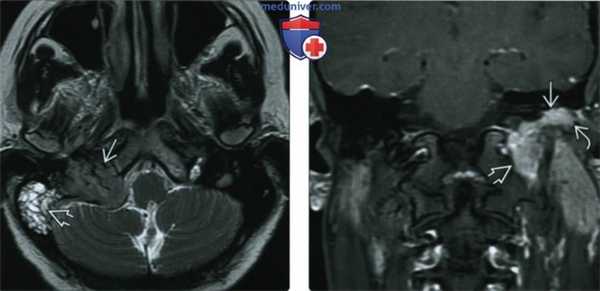

(Слева) При МРТ Т1 ВИ в аксиальной проекции определяется мелкая шваннома правого яремного отверстия. Обратите внимание на характерное отсутствие «пустот потока» вследствие высокой скорости кровотока, что помогает дифференцировать это новообразование от чаще встречающейся параганглиомы яремного гломуса. Мелкие новообразования бывает трудно дифференцировать от асимметричной луковицы яремной вены.

(Справа) При MPT Т1 FS с КУ в аксиальной проекции у этого же пациента наблюдается неоднородное контрастирование шванномы. В крупных опухолях может выявляться интрамуральный неконтрастируемый кистозный компонент.

(Слева) При МРТ Т1 FS c КУ в аксиальной проекции определяется веретеновидная равномерно контрастируемая шваннома правого яремного отверстия, распространяющаяся в соседнюю цистерну. У большинства таких пациентов диагностируется сопутствующая сенсоневральная тугоухость.

(Справа) При корональной МРТ Т1 ВИ FS с КУ определяется неравномерно контрастируемое дольчатое объемное образование, развившееся из яремного отверстия. Обратите внимание на характерное верхне-медиальное направление роста опухоли к стволу головного мозга. В крупных опухолях могут определяться неконтрастируемые участки, представляющие собой интрамуральные кисты.